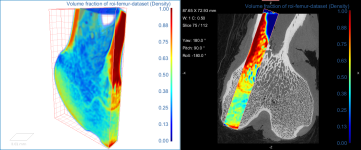

Comparison of volume fraction scalar map (on left) with vector-based field of anisotropy (on right)